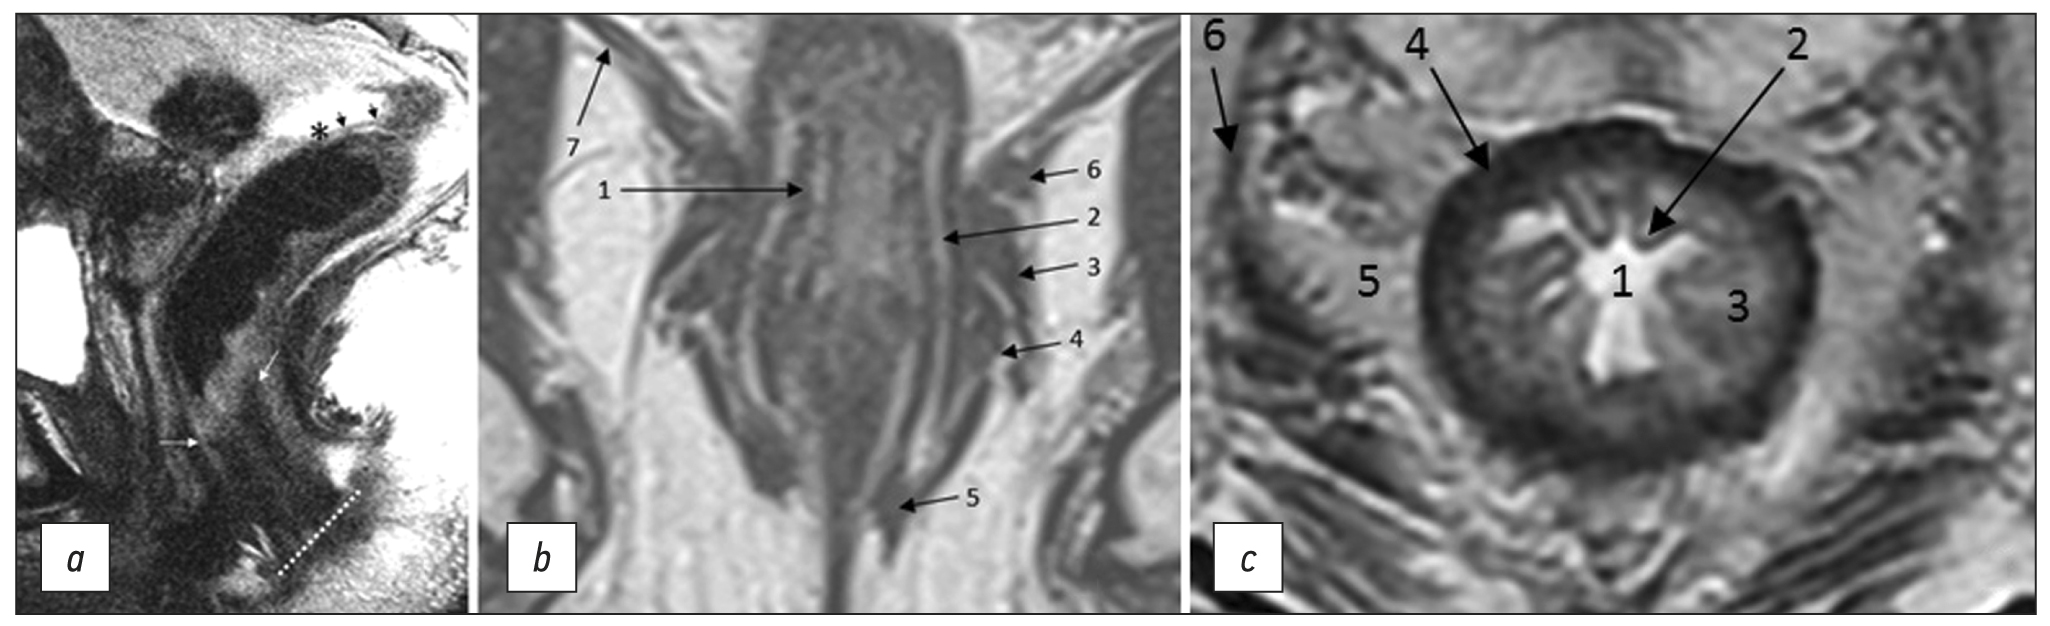

- Bogveradze N., Snaebjornsson P., Grotenhuis B.A., et al. MRI anatomy of the rectum: Key concepts important for rectal cancer staging and treatment planning // Insights Imaging. 2023. Vol. 14, N 1.Р. 13. doi: 10.1186/s13244-022-01348-8

- Santiago I., Figueiredo N., Parés O., et al. MRI of rectal cancer: Relevant anatomy and staging key points // Insights Imaging. 2020. Vol. 11, N 1. Р. 100. doi: 10.1186/s13244-020-00890-7